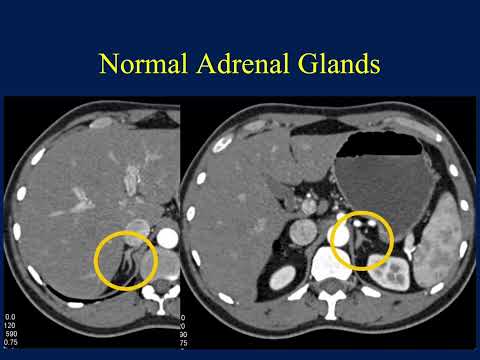

CT of the Adrenal Mass: A Challenging Diagnosis Becomes Even More Difficult - Part 1

Part 2: https://youtu.be/_rSKDHGHmZI Part 3: https://youtu.be/9FWWpUIuJ1M Part 4: https://youtu.be/duV56-r9peo For more, visit our website at https://www.CTisus.com Check out the apple App Store for CTisus apps https://tinyurl.com/y2pyjzhv Keep in Touch at: Facebook: http://facebook.com/CTisus Twitter: http://twitter.com/CTisus Instagram: http://instagram.com/CTisus_radiology Pinterest: http://pinterest.com/CTisus_radiology LinkedIn: http://linkedin.com/company/CTisus CTisus.com is an informational and educational radiological resource dedicated to CT scanning. Founded by Elliot K. Fishman, M.D. The website provides the latest information regarding radiology technology and 3D imaging. It features a library of content, including lectures and case studies, as well as medical illustrations and other radiology resources.